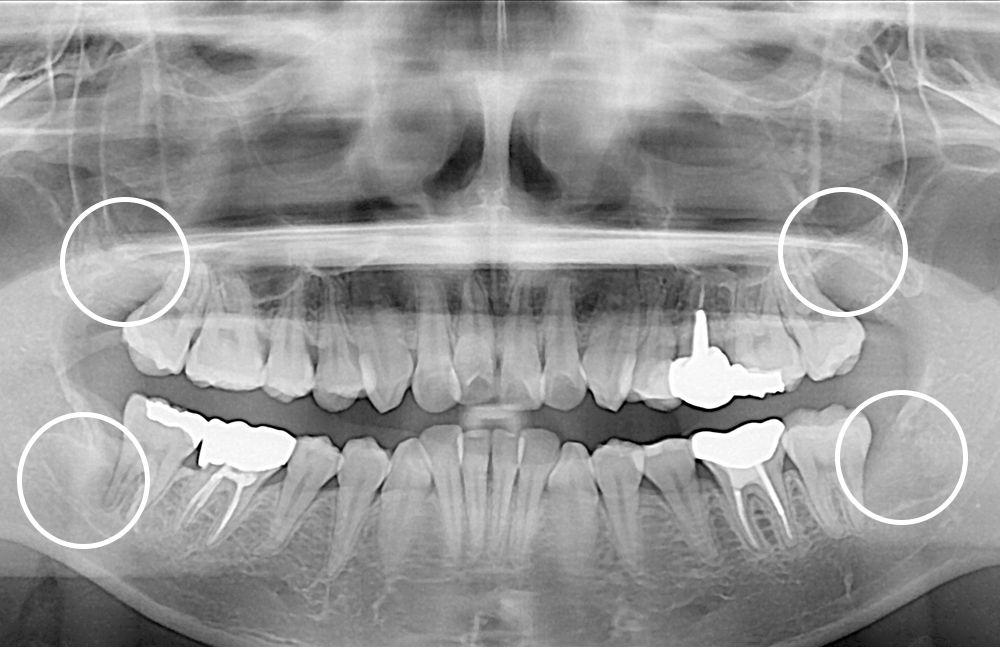

[사랑니] 매복 사랑니 발치

치료후 : 2021-05-12

세종치과는 구강악안면외과학 박사이신 원장님이 발치하는 치과입니다.